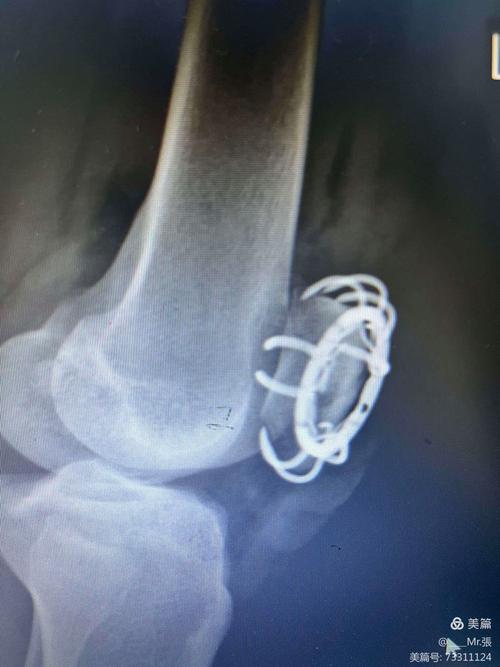

醫師會透過X光、電腦斷層(CT)掃描等影像檢查,精確評估骨折的類型、位置、移位程度及穩定性,再與患者充分溝通後,共同決定最合適的治療方案。